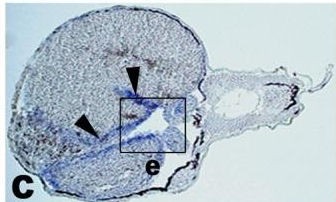

???displayGene.symbol???: myh11

???displayGene.name???: myosin heavy chain 11

Diseases: Disease Ontology: megacystis-microcolon-intestinal hypoperistalsis syndrome

AORTIC ANEURYSM, FAMILIAL THORACIC 4; AAT4